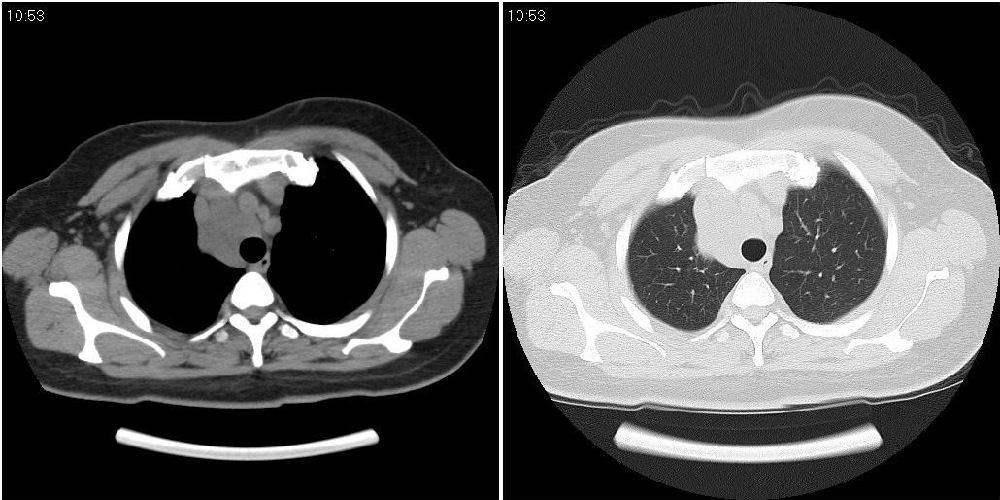

标题: CT24795:女性,47岁,右下腿静脉静脉曲张手术前体检,发现 [打印本页]

标题: CT24795:女性,47岁,右下腿静脉静脉曲张手术前体检,发现

囊性无明显占位效应:1淋巴管囊肿2畸胎瘤(其上部见小钙化)3前肠囊肿

右上纵隔囊性占位性病变;考虑淋巴管囊肿,不排除支气管囊肿。

支气管囊肿、囊性畸胎瘤、肠源性囊肿均有可能。

右上纵隔囊性占位性病变;考虑淋巴管囊肿,不排除支气管囊肿。 建议增强。

考虑淋巴管囊肿,不排除前肠囊肿。